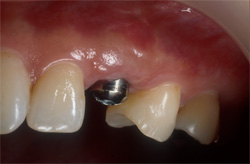

| インプラント用の義歯を2本あるいは、それ以上のインプラントとアタッチメントにより接続します。 |

| オーバーデンチャー ※インプラントと義歯のコンビネーション |

ボールアバットメント |